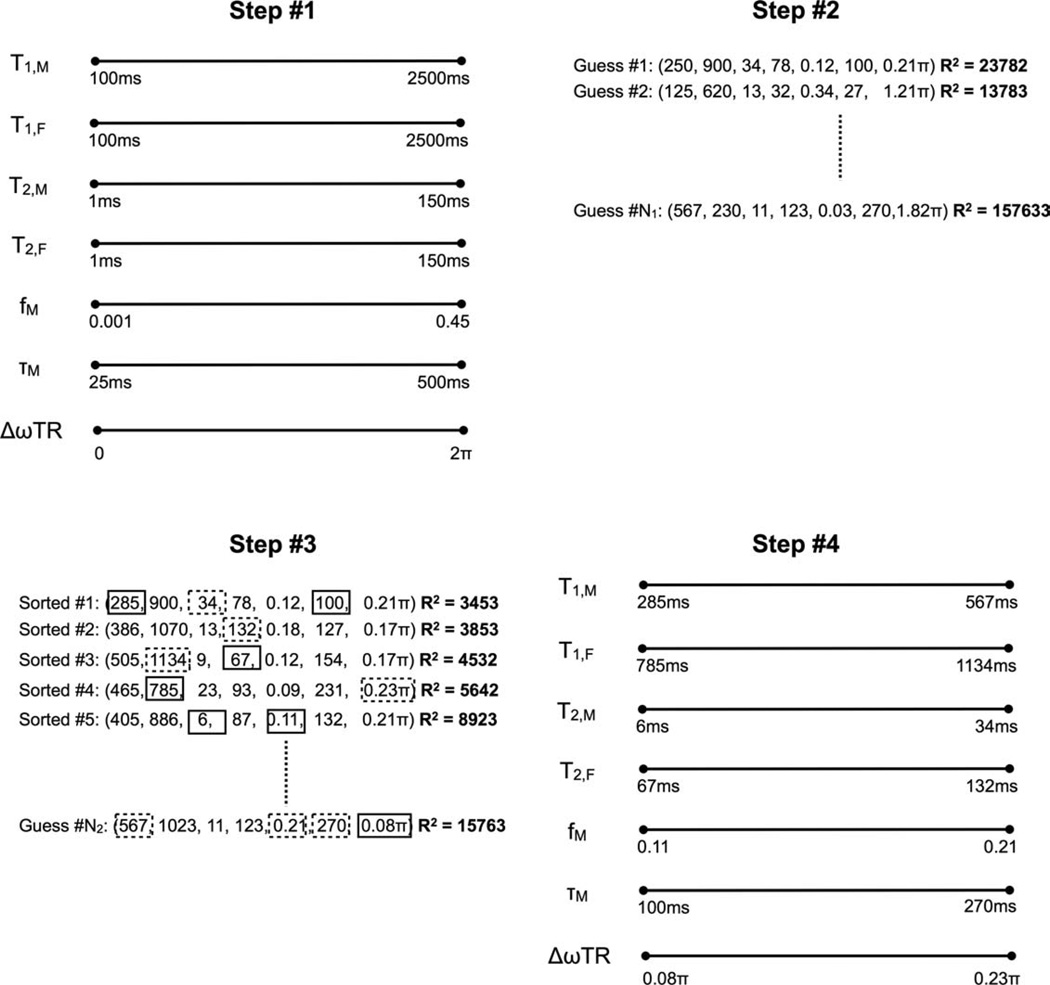

Building on this first simulation, the accuracy and precision of subsequently derived multicomponent mcDESPOT parameters (T1,F, T2,F, T1,M T2,M, τM and fM, with δω = 0) was investigated. Two-component SPGR, IR-SPGR, and bSSFP data were generated as fM was varied from 0.04 to 0.2 in increments of 0.02; and for κ values of 0.8, 1.00, and 1.20. Modeled “acquisition” parameters were: SPGR: TR = 5.4 msec, αP = {2, 4, 6, 8, 10, 12, 14, 16, and 18}°; IR-SPGR: TR = 5.4 msec, TI = 450 msec, αP = 5°, NRF = 64; bSSFP: TR = 3.5 msec, αP = {8, 16, 24, 32, 40, 48, 56, 64, 72}°. For the analysis κ was first estimated from the IR-SPGR and SPGR data and then used in the multicomponent model fitting. As above, 65,000 estimates of κ, T1,F, T2,F, T1,M, T2,M, τM and fM were evaluated at each fM and κ combination. For comparison, the simulation was also performed with κ set to one (i.e., no assumed B1 inhomogeneity). The nonlinear mcDESPOT fitting was performed using the stochastic region contraction approach described in Appendix B and illustrated in Fig. 3. As effects of B0 inhomogeneity were not included in the simulation, only a six-parameter fit for T1,F, T2,F, T1,M, T2,M, τM, and fM was performed.

FIG. 3.

Graphical illustration of the stochastic region contraction fitting routine used to fit the two-component SPGR and bSSFP signal models to the acquired multiple flip angle imaging data.

APPENDIX B

Nonlinear Fitting of the Two-Component SPGR and bSSFP Signal Models to Acquired Data

To fit Eqs. (A7) and (A8) to the multiple flip angle SPGR and bSSFP data, a stochastic region contraction approach (26) is used. As illustrated in Fig. 3, this approach begins by defining the expected search-space extents, e.g., 100 msec ≤ T1,M, T1,F ≤ 2500 msec; 1 msec ≤ T2,M, T2,F ≤ 150 msec; 0.0 ≤ fM ≤ 0.45; and 25 ≤ τM < 500 msec (and 0.0 ≤ δω ≤ 1/TR). Because of the periodic nature of the (σRF + δω) in Eq. (A3), we can limit the range of δω investigated to 0 ≤ δω ≤ 1/TR, i.e., δω =δω + 2 repeating with a frequency of 1/TR. N1 samples of T1,M, T1,f, T2,M, T2,F, fM, and τM (and δω) are then randomly chosen from these uniform distributions and for each combination, the theoretical SPGR and bSSFP signal curves generated, normalized (with respect to the mean value), and the sum-of-squares residuals are calculated. To calculate the residuals, the acquired SPGR data is normalized with respect to the mean signal intensity; and each acquired bSSFP dataset is also normalized with respect to their respective means. The theoretical SPGR and bSSFP are likewise normalized. The cumulative sum-of-squares are then calculated across all data-points.

The N1 combinations are then rank sorted by increasing residual and from the top N2 combinations, the minimum and maximum sampled value of each parameter is determined. These values are then used to update the extents of search-space and the sampling process repeated. In this way, the search-space slowly contracts to the globally optimum solution. The algorithm continues until the difference between the minimum and maximum value of each parameter falls below a predefined threshold (Td) or some number (NT) of iterations are performed and the top solution upon termination is taken as the solution. Throughout this work, we use N1 = 5000, N2 = 50, Td = 0.5% and NT = 8. These parameters have been arrived at through an ad hoc optimization study.